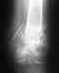

потеряны 2,3,4,5 пальцы на левой руке.культи на уровне дистального отдела основных фаланг.

есть ли у современной медицины возможности для восстановления пальцев.какими методами и какие это будут пальцы в случае восстановления.подскажите куда обратиться.заранее благодарен за ответ